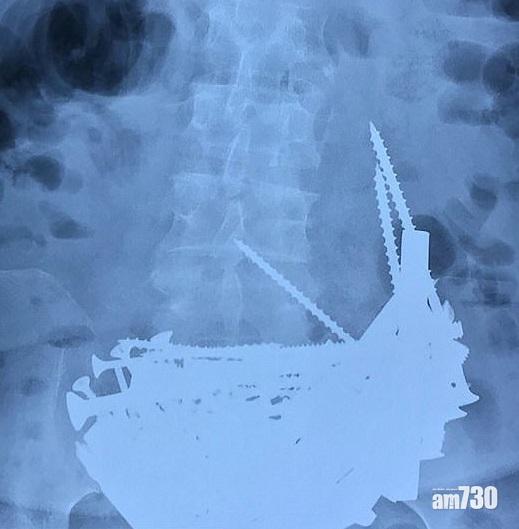

俗語有云「缺甚麼補甚麼」,俄羅斯東南部烏蘭烏德市(Ulan-Ude)一名74歲貧血老婦就想出食鐵補鐵質!她於14年前開始食長釘、鏍絲和銀鍊等,近日因高燒入院,照X光時,醫護人員發現其胃部有堆異物(圖),於是為她施手術,從其胃裡取出逾152件鐵製品,神奇的是,她的胃部和喉嚨皆沒有嚴重受損,現正留院觀察。